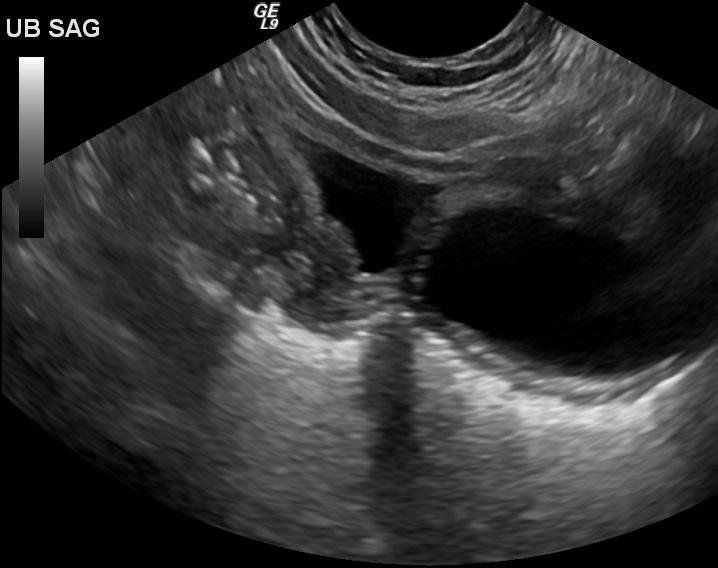

Courvoisier's GB

Distension without wall thickening

due to obstruction distal to the cystic duct

*Panncreatic head mass

* Duodenal papilla mass

*CBD mass